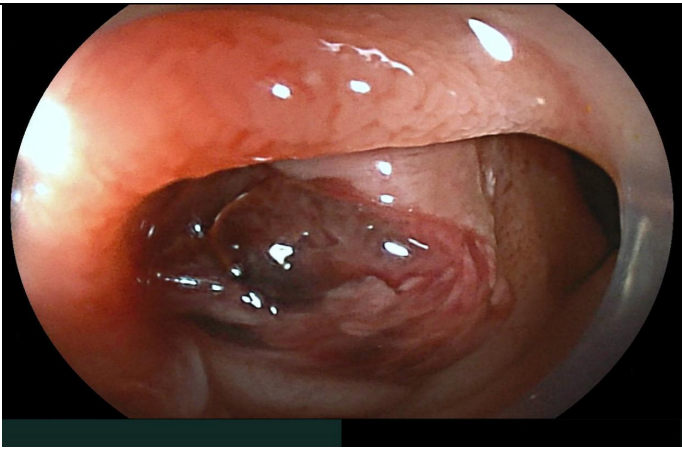

The patient was admitted with a severe IDA, confirmed by laboratory tests (Hb 4.3 g/dL, MCV 76 fl, ferritine 3 ng/ml), with no blood traces at rectal examination. Hemodynamical stability was maintained during all hospitalization; six blood transfusions was overall infused. Taking into account the previous investigations, a video capsule endoscopy (VCE) was performed showing minimal traces of red blood in the proximal small bowel lumen, without obvious mucosal lesions (Figure A). We decided to further investigate the small bowel with a per-oral device assisted enteroscopy (DAE), with identified a bulging with an adherent clot (Figure B) in the distal duodenum. The clot was gently washed with no signs of ongoing bleeding; its removal exposed a deep ulceration containing a yellowish structure behind (Figure C). An urgent angio-CT confirming the aorto-duodenal fistula (Fig. D) was performed and the patient was transferred to Vascular Surgery Department for surgical treatment.

B. Per-oral device assisted enteroscopy: mucosal bulging with adherent clot.